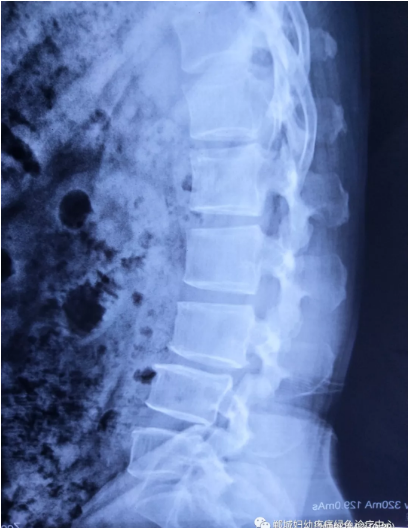

不經(jīng)意間聽到有人說醫(yī)院疼痛科可以不吃藥不打針,用無痛苦、無創(chuàng)傷的方法治療腰痛。陳女士就抱著試試看的心理來到了鄲城縣婦幼保健院疼痛科,疼痛科時慶祥主任詳細(xì)了解病情,結(jié)合腰椎磁共振及體征后告訴陳女士她不用手術(shù),通過腰椎脊柱定位周期減壓牽引系統(tǒng)(外星艙)也能解決腰痛、腰椎滑脫、腰椎反弓這些問題。陳女士未曾想到經(jīng)過十五天的治療后腰部及下肢放射性疼痛癥狀基本消失。陳女士感到十分激動與感謝,就在當(dāng)?shù)匦l(wèi)生院做了一個腰椎正側(cè)位x片和之前的片子作對比,發(fā)現(xiàn)腰椎滑脫明顯改善。她說道:感謝鄲城縣婦幼保健院疼痛科的所有醫(yī)護人員、感謝外星艙脊柱減壓治好了我的腰痛,也感謝告訴我來這里的人,她的一句話,讓我省了好幾萬元的手術(shù)費!

治療后